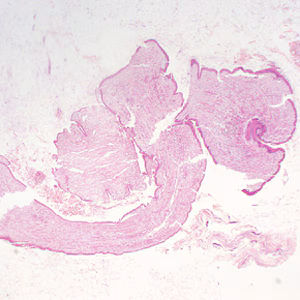

Case #333 – October, 2012

A 68-year-old woman underwent a routine screening mammogram, which revealed calcifications in the right breast. Biopsy specimens were collected and sent to Pathology for histological work-up. Figures A–D show what was observed at 20x, 100x, 200x, and 400x magnification respectively by the attending pathologist on one of the slides stained with hematoxylin and eosin (H&E). What is your diagnosis? Based on what criteria?

Figure A